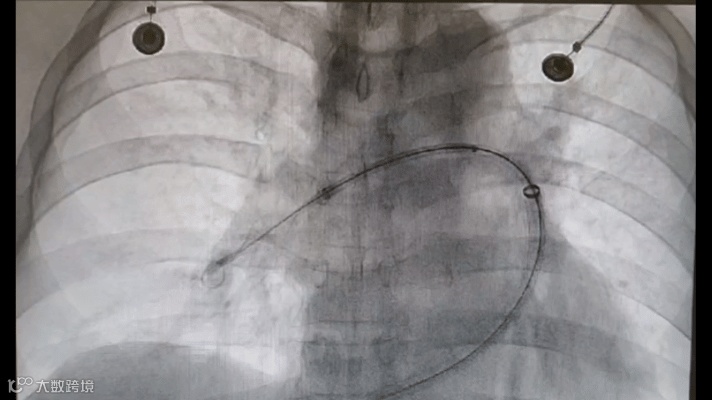

再将Tendvia®肺动脉取栓支架沿导丝通过抽吸导管向前推送,精确导入到患者的肺动脉血栓部位。随后回撤输送鞘管,支架自动膨开。

支架自动膨开